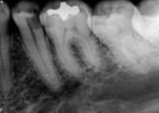

antes depois